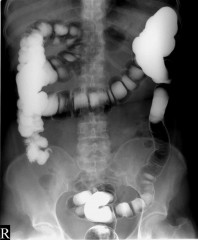

უკანასკნელი სამეცნიერო კვლევის შედეგად დამტკიცდა, რომ მუცლის შებერილობის მიზეზი მხოლოდ გადაჭარბებული დოზით საკვების მიღება არ არის - ის შესაძლოა ბევრად უფრო სერიოზული მიზეზით იყოს განპირობებული. ადამიანების უმრავლესობას წარმოდგენაც კი არ აქვს, რომ მუცლის შებერილობის ერთ-ერთი მთავარი გამომწვევი მიზეზი წებოვანას აუტანლობაა. მუცლის შებერილობა თქვენი ნაწლავების ბაქტერიების რეაქციაა წებოვანაზე...

ადამიანები, რომლეთათვის ეს პრობლემა ნაცნობია, ასევე შეიძლება იტანჯებოდნენ ცეილაკიისგან, რომელიც საჭლის მონელებასთან დაკავშირებული პრობლემების ძირითადი გამომწვევი მიზეზია. მნიშვნელოვანია აღინიშნოს, რომ წებოვანას მრავალი საკვები პროდუქტი შეიცავს (მაგ: ქერი, ხორბალი და ჭვავი).

ცეილაკიით შეპყრობილი ადამიანებისთვის ძალიან კარგადაა ცნობილი მუცლის ტკივილი, დიარეა, მუცლის შებერილობა და ქრონიკული დაღლილობა.